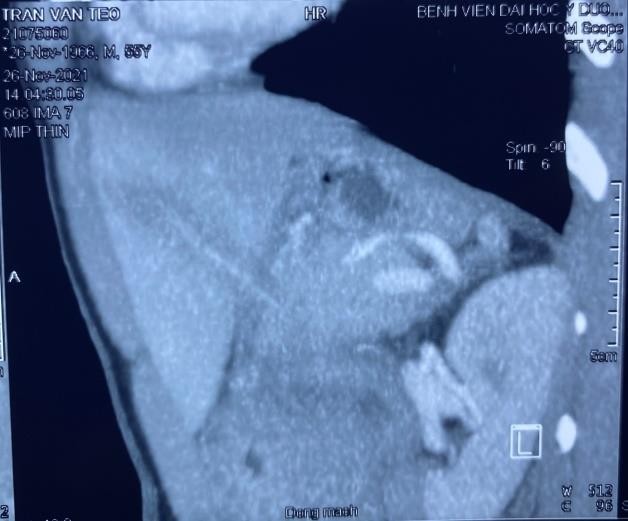

Bệnh nhân Trần Văn T. , 55 tuổi, địa chỉ tại Thủy Xuân, thành phố Huế nhập viện tại Trung tâm cấp cứu đa khoa và đột quỵ, Bệnh viện Trường Đại Học Y Dược Huế vì tình trạng đau bụng vùng thượng vị chếch hạ sườn phải. Khai thác tiền sử cho thấy bệnh nhân có thói quen ngậm tăm sau khi ăn và thỉnh thoảng trong khi đi ngủ, tình trạng đau bụng đã kéo dài từ khoảng 5 ngày nay. Thăm khám lâm sàng cho thấy bệnh nhân tỉnh táo, nhiệt độ 37,8oC, đau bụng chủ yếu vùng thượng vị chếch hạ sườn phải, ấn vào cảm giác đau nhiều hơn. Xét nghiệm máu cho thấy bệnh nhân đang có hội chứng nhiễm trùng với bạch cầu tăng 12,58 x 109/l (N=63%) và CRP tăng 18,94 mg/l. Hình ảnh chụp cắt lớp vi tính bụng cho thấy hình ảnh một dị vật dài 65mm (khả năng tăm tre) đâm xuyên vào phần gan trái và thân tụy, thâm nhiễm viêm xung quanh tạo thành ổ tụ dịch kích thước 34x28mm.

Hình 1: Hình ảnh dị vật đâm xuyên vào gan trái và thân tụy trên phim chụp cắt lớp vi tính

Đối với các dị vật đường tiêu hóa như tăm tre, vai trò của chụp Xquang bụng thường hầu như ít có giá trị. Trong trường hợp này, vai trò của siêu âm hoặc chụp cắt lớp vi tính bụng rất có giá trị trong việc phát hiện tăm tre bằng hình ảnh dị vật tăng âm trên siêu âm hoặc dị vặt tăng tỷ trọng trên hình ảnh cắt lớp vi tính. Quan điểm của Haidong Chen cho rằng đối với những cơ sở y tế có trang bị máy chụp cắt lớp vi tính có thể dựng hình ảnh được thì có thể xác định mối liên quan giữa dị vật (tăm tre) và các mạch máu ở thùy gan trái dễ dàng, điều này rất quan trọng vì trong trường hợp bệnh nhân được chỉ định phẫu thuật sẽ giúp cho phẫu thuật viên có thể đưa ra chẩn đoán và tiên lượng trước mổ một cách tương đối chính xác, làm cho hiệu quả của cuộc phẫu thuật sẽ thành công hơn.